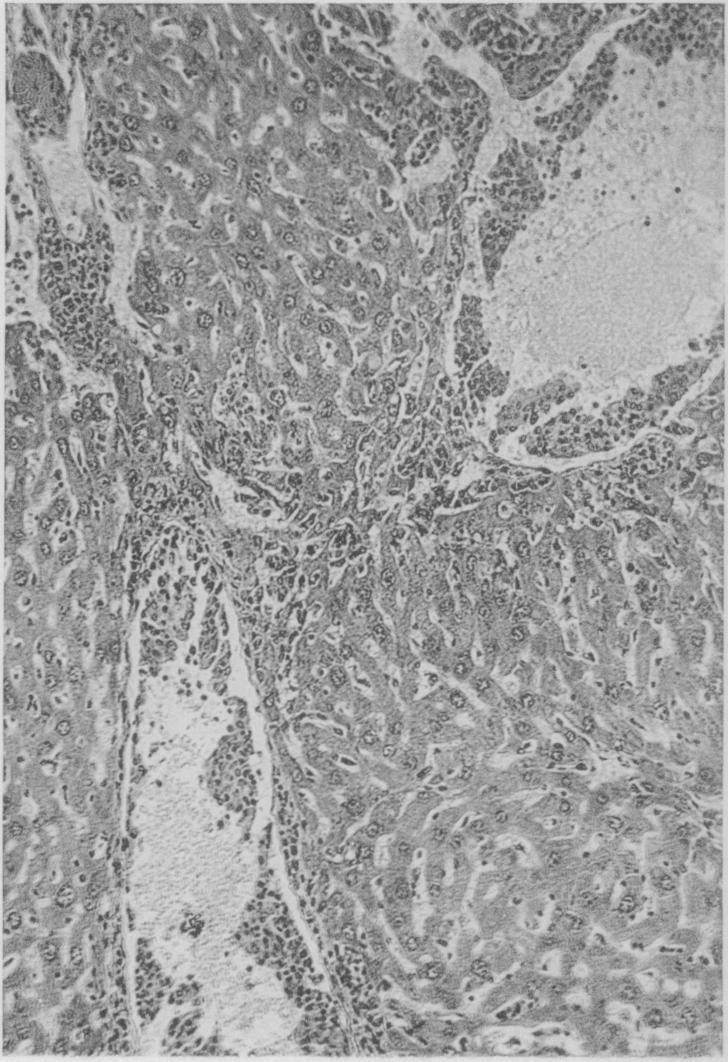

A Series of spontaneous tumors in Mice with Observations on the Influence of Heredity on the Frequency of their Occurrence.

J Med Res. 1909 Oct;21(3):479-518.13.

PMID:19971929

原文链接:https://pmc.ncbi.nlm.nih.gov/articles/PMC2099039/